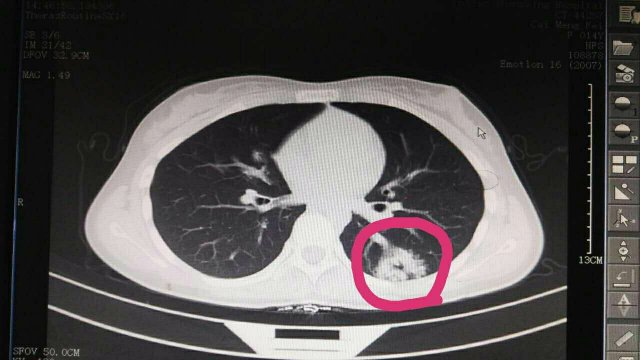

蔡**,女,14歲因“反覆頭暈3年余”,求診莆田及莆田各三級(jí)醫(yī)院,做過(guò)很多輔助檢查,均未確診,于2017-2-26日就診我院門診,接診是我院兒科林富醫(yī)師,經(jīng)過(guò)認(rèn)真仔細(xì)查體,發(fā)現(xiàn)患兒左側(cè)肩胛骨可聞及Ⅱ-Ⅲ/Ⅵ級(jí)收縮期雜音,為明確診斷,即刻請(qǐng)我院莊姞副主任醫(yī)師(原莆田市Di一醫(yī)院NICU主任)會(huì)診,查胸部CT發(fā)現(xiàn)左肺下葉背段血管畸形。莊姞副主任醫(yī)師告訴我們,部分型肺血管畸形如果不認(rèn)真查體是很難查體的到,年輕醫(yī)師能如此仔細(xì)查體,確診多家醫(yī)院未確診的疾病,不得不對(duì)林醫(yī)生豎起大拇指,通過(guò)此次經(jīng)歷,可見臨床醫(yī)生必須熟練掌握臨床三基的重要性。